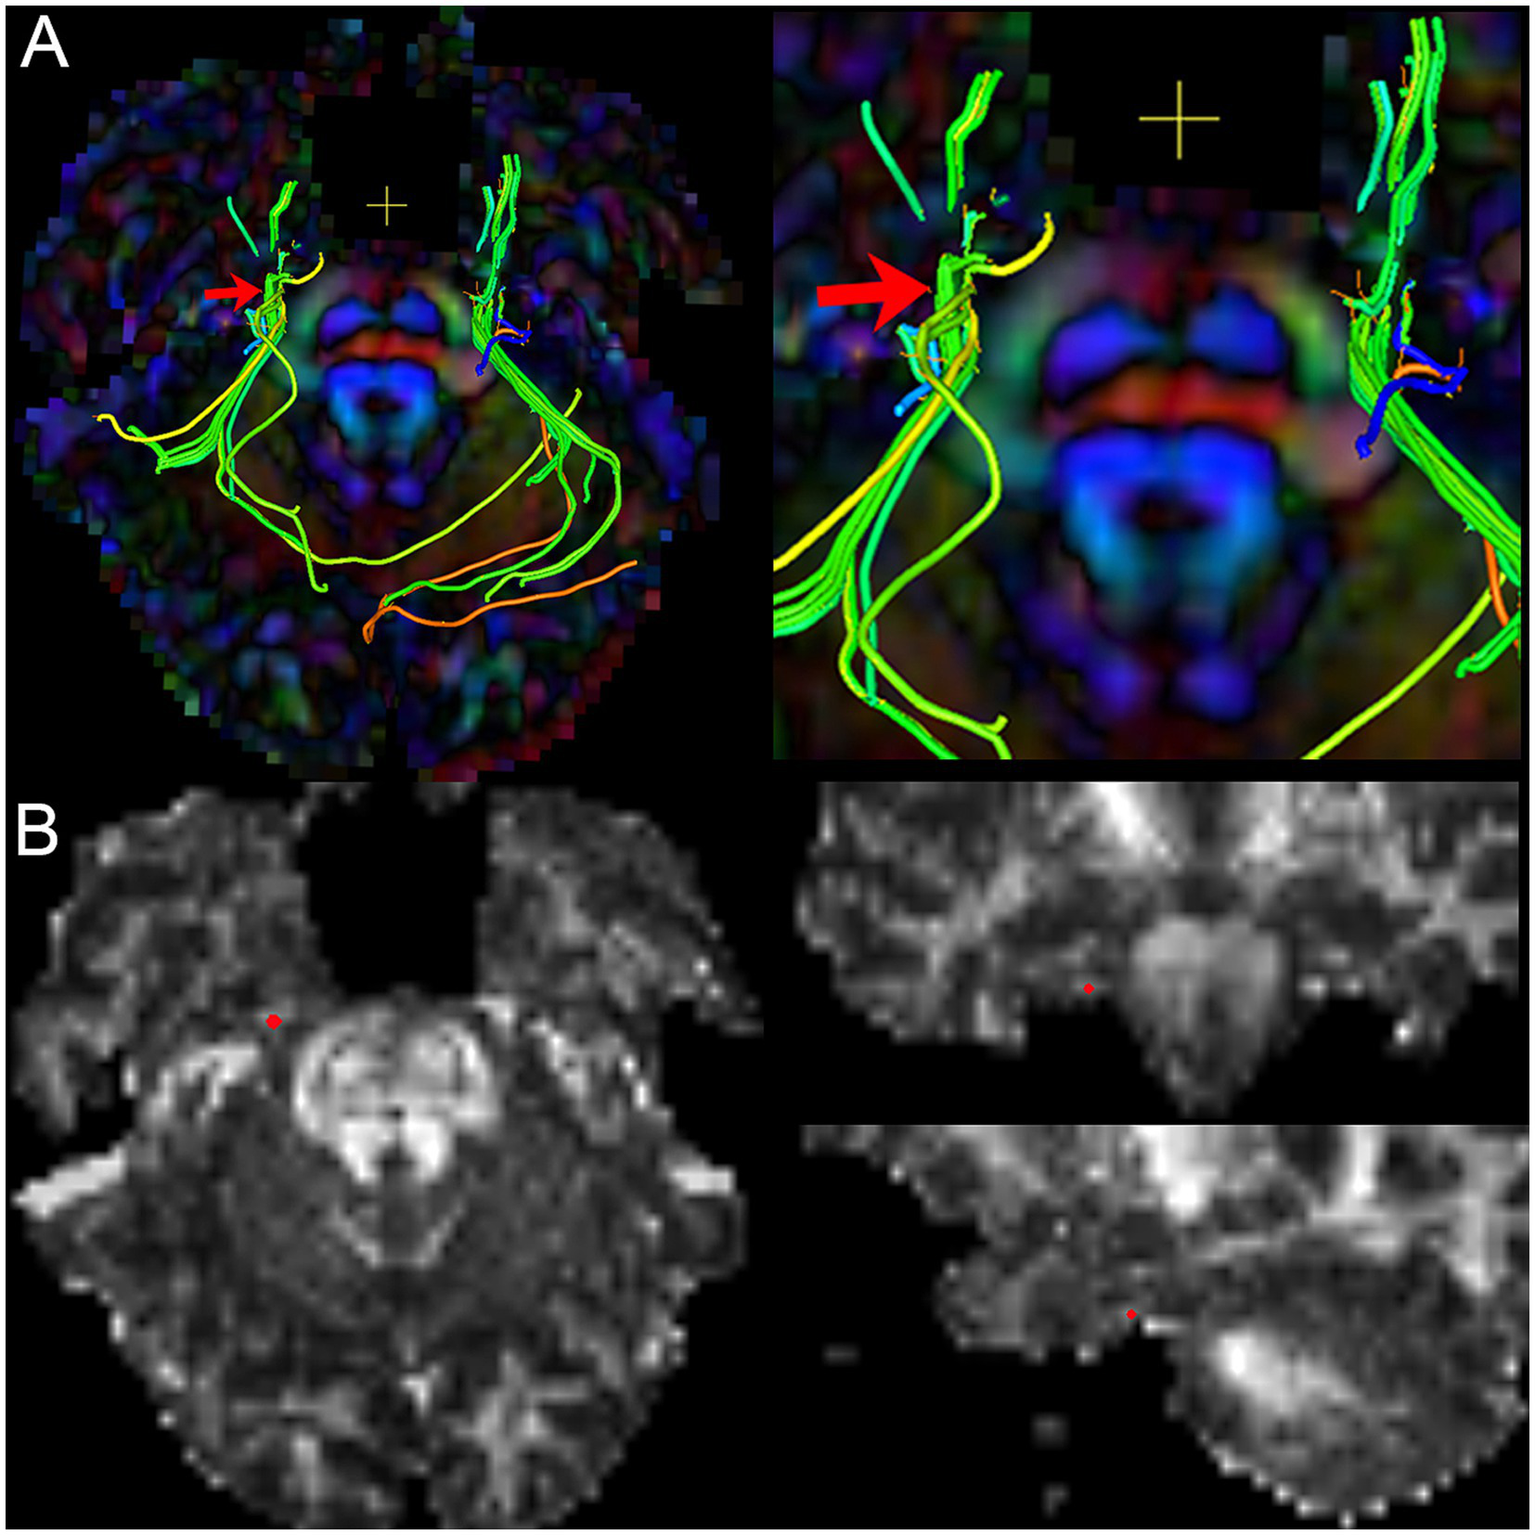

Figure 3

The image shows the extraction of diffusivity metrics on the bilateral CNV tracts. (A) the fused image of FA color-map and the reconstruction of CNV tracts, and image (right) is the focal magnification of image (left); (B) the position of the centroid on the CNV tract in axial, sagittal, and coronal view of FA map. Red arrow and red point: the position of the centroid.

To obtain the diffusivity metrics (FA, MD, AD, and RD) of CNV (Figure 3), the centroid was placed on the nerve tract in the successive coronal scalar maps and its position validated on the 3D planes and the CNV tracts. In total, 1–3 DTI scans (preoperative, postoperative, and follow-up) were performed in each TN patients.